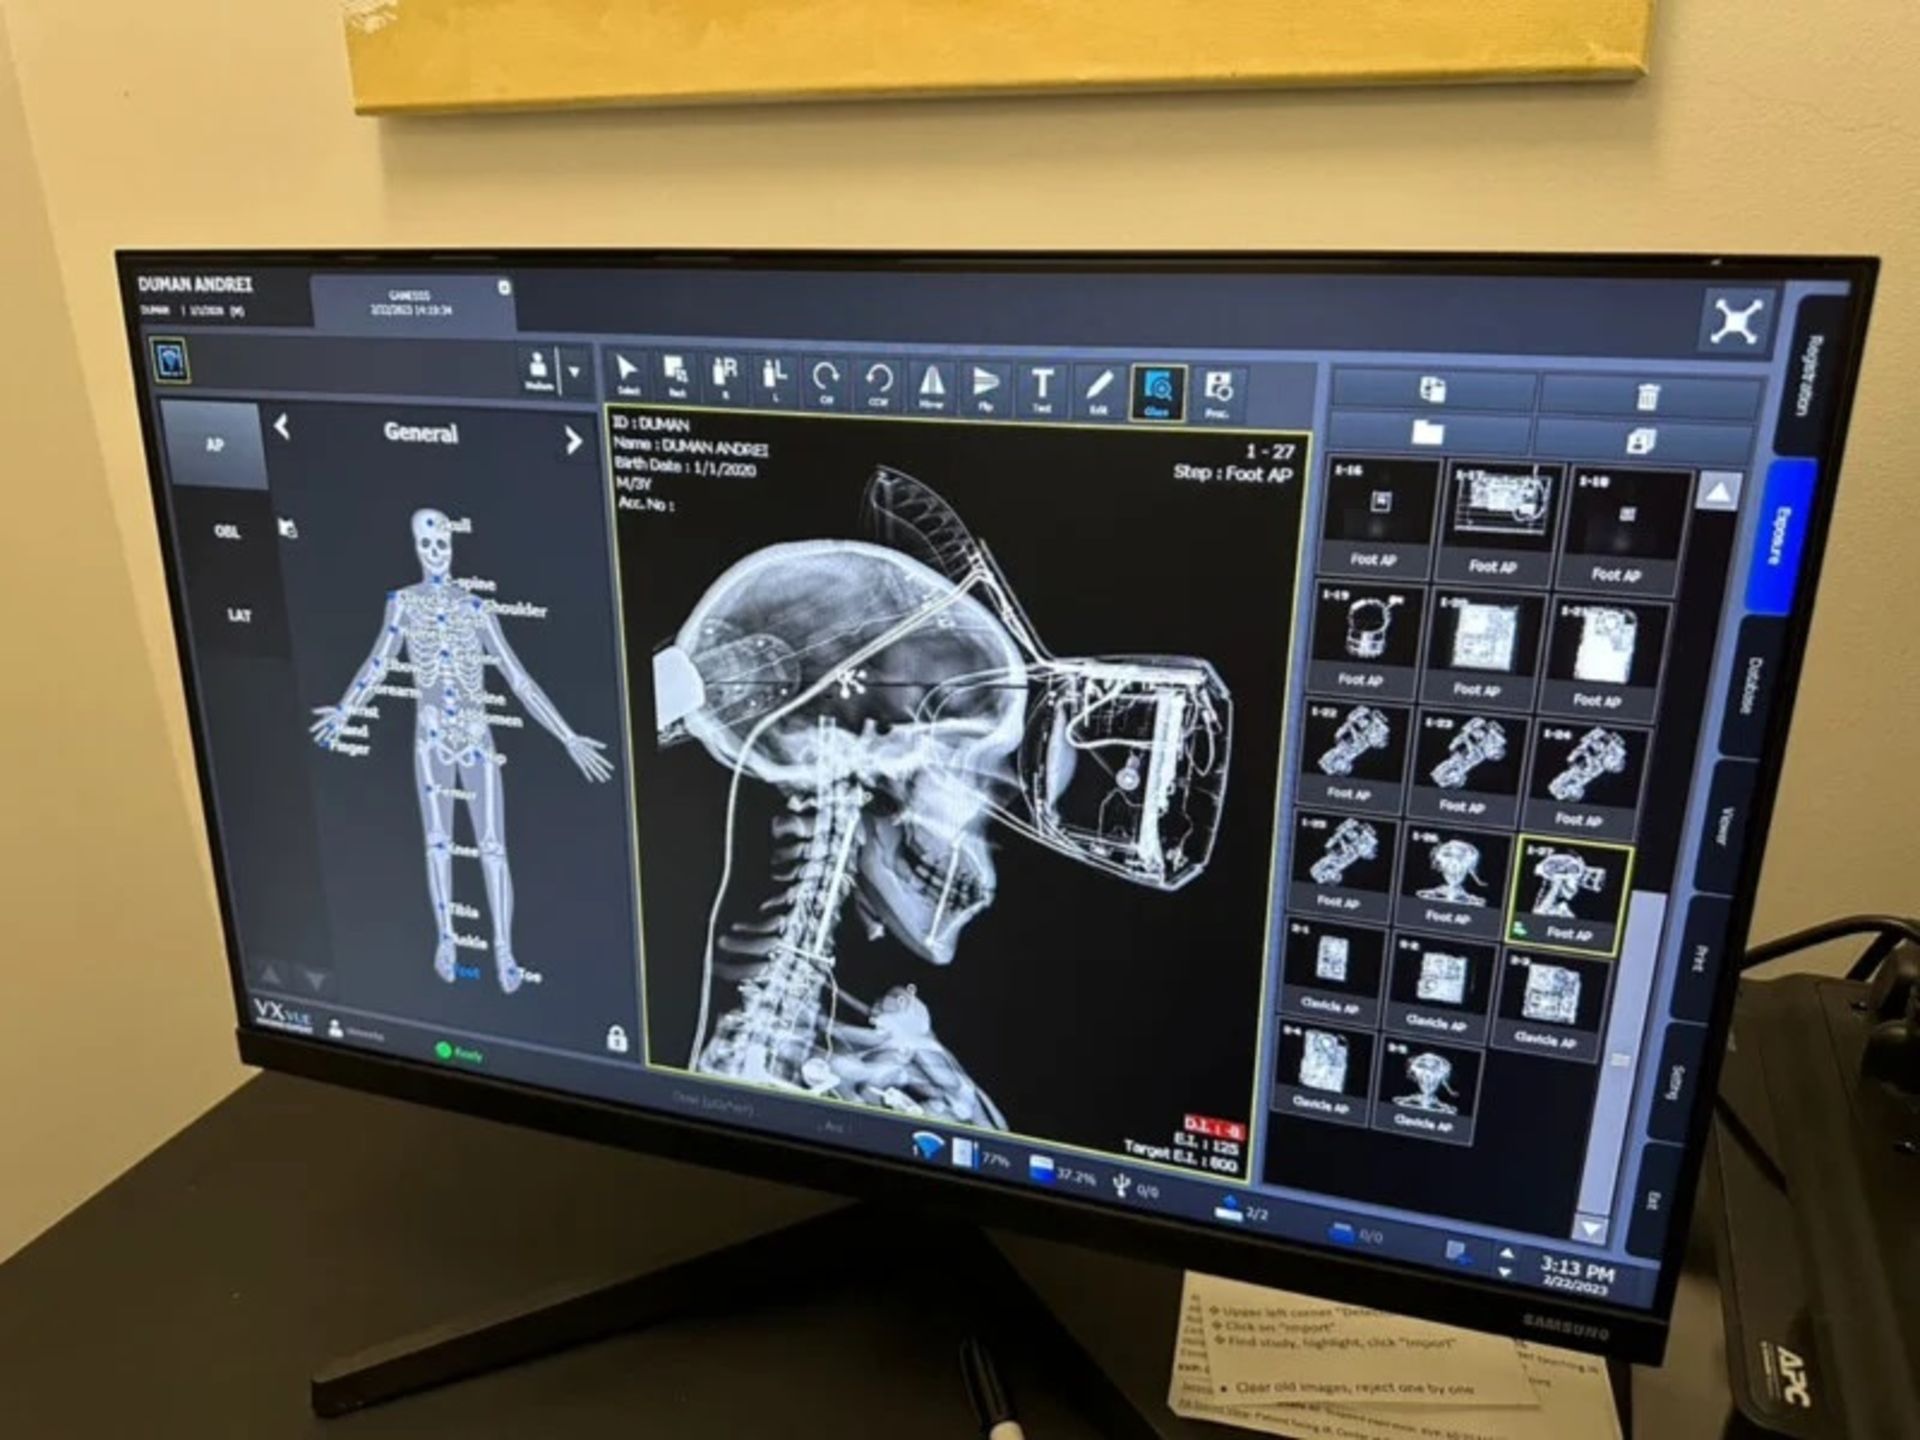

آندری دومن (Andrei Duman)، عکاس تجاری، پروژه «اشعه ایکس» را بهروشی نو و خلاقانه با هدف نمایش آنچه در زیر پوست محصولاتی که مردم در زندگی روزمره از آنها استفاده میکنند، بهوجود آورده است.

دومن از لگو، کنسولها و کنترلهای بازی، پهپادها و هدفون، طیف گستردهای از محصولات اپل و غیره عکاسی کرده است. او میگوید یکی از زمانبرترین بخشهای پروژه، انتخاب محصولات مناسب برای قرار گرفتن در معرض اشعه ایکس است. برای مثال زمان زیادی طول کشید تا او تمام مدلهای مختلف آیفون را پیدا کند، زیرا مردم اغلب مدلهای قدیمی را پس از چند سال کنار میگذارند.